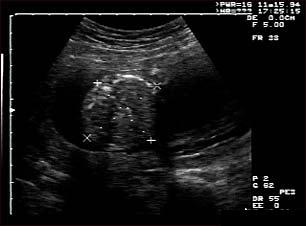

Ecografia fetala